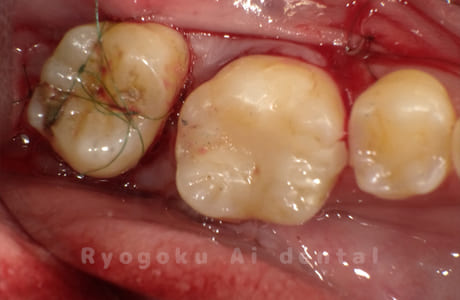

Case27

歯牙移植術直後咬合面

-

歯牙移植術後咬合面

歯牙移植術前側面

歯牙移植術中側面

歯牙移植術後側面

- 原因

- 重度カリエス

- 治療内容

- 自家歯牙移植、部分矯正

- 治療費用

- 220,000円(移植費用)

110,000円(部分矯正費用)

虫歯が大きく、保存不可能となった歯を上の親知らずと交換する自家歯牙移植を行いました。移植歯が小ぶりであったため、部分矯正を行い問題なく噛み合い、経過良好です。